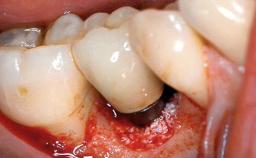

The fracture of an implant after it has been restored is one of the most severe complications. It most frequently occurs in partially edentulous jaws (1.5%). Most implant fractures involve implants with a diameter of 3.75 mm made of commercially pure titanium (Eckert 2010). Unfortunately, many cases are not reported or documented by the clinicians involved in resolving the problems created by the fracture. This case report describes the management of an implant fracture at site 36 in a middle-aged male patient. The implant had been restored with a screw-retained metal-ceramic crown.